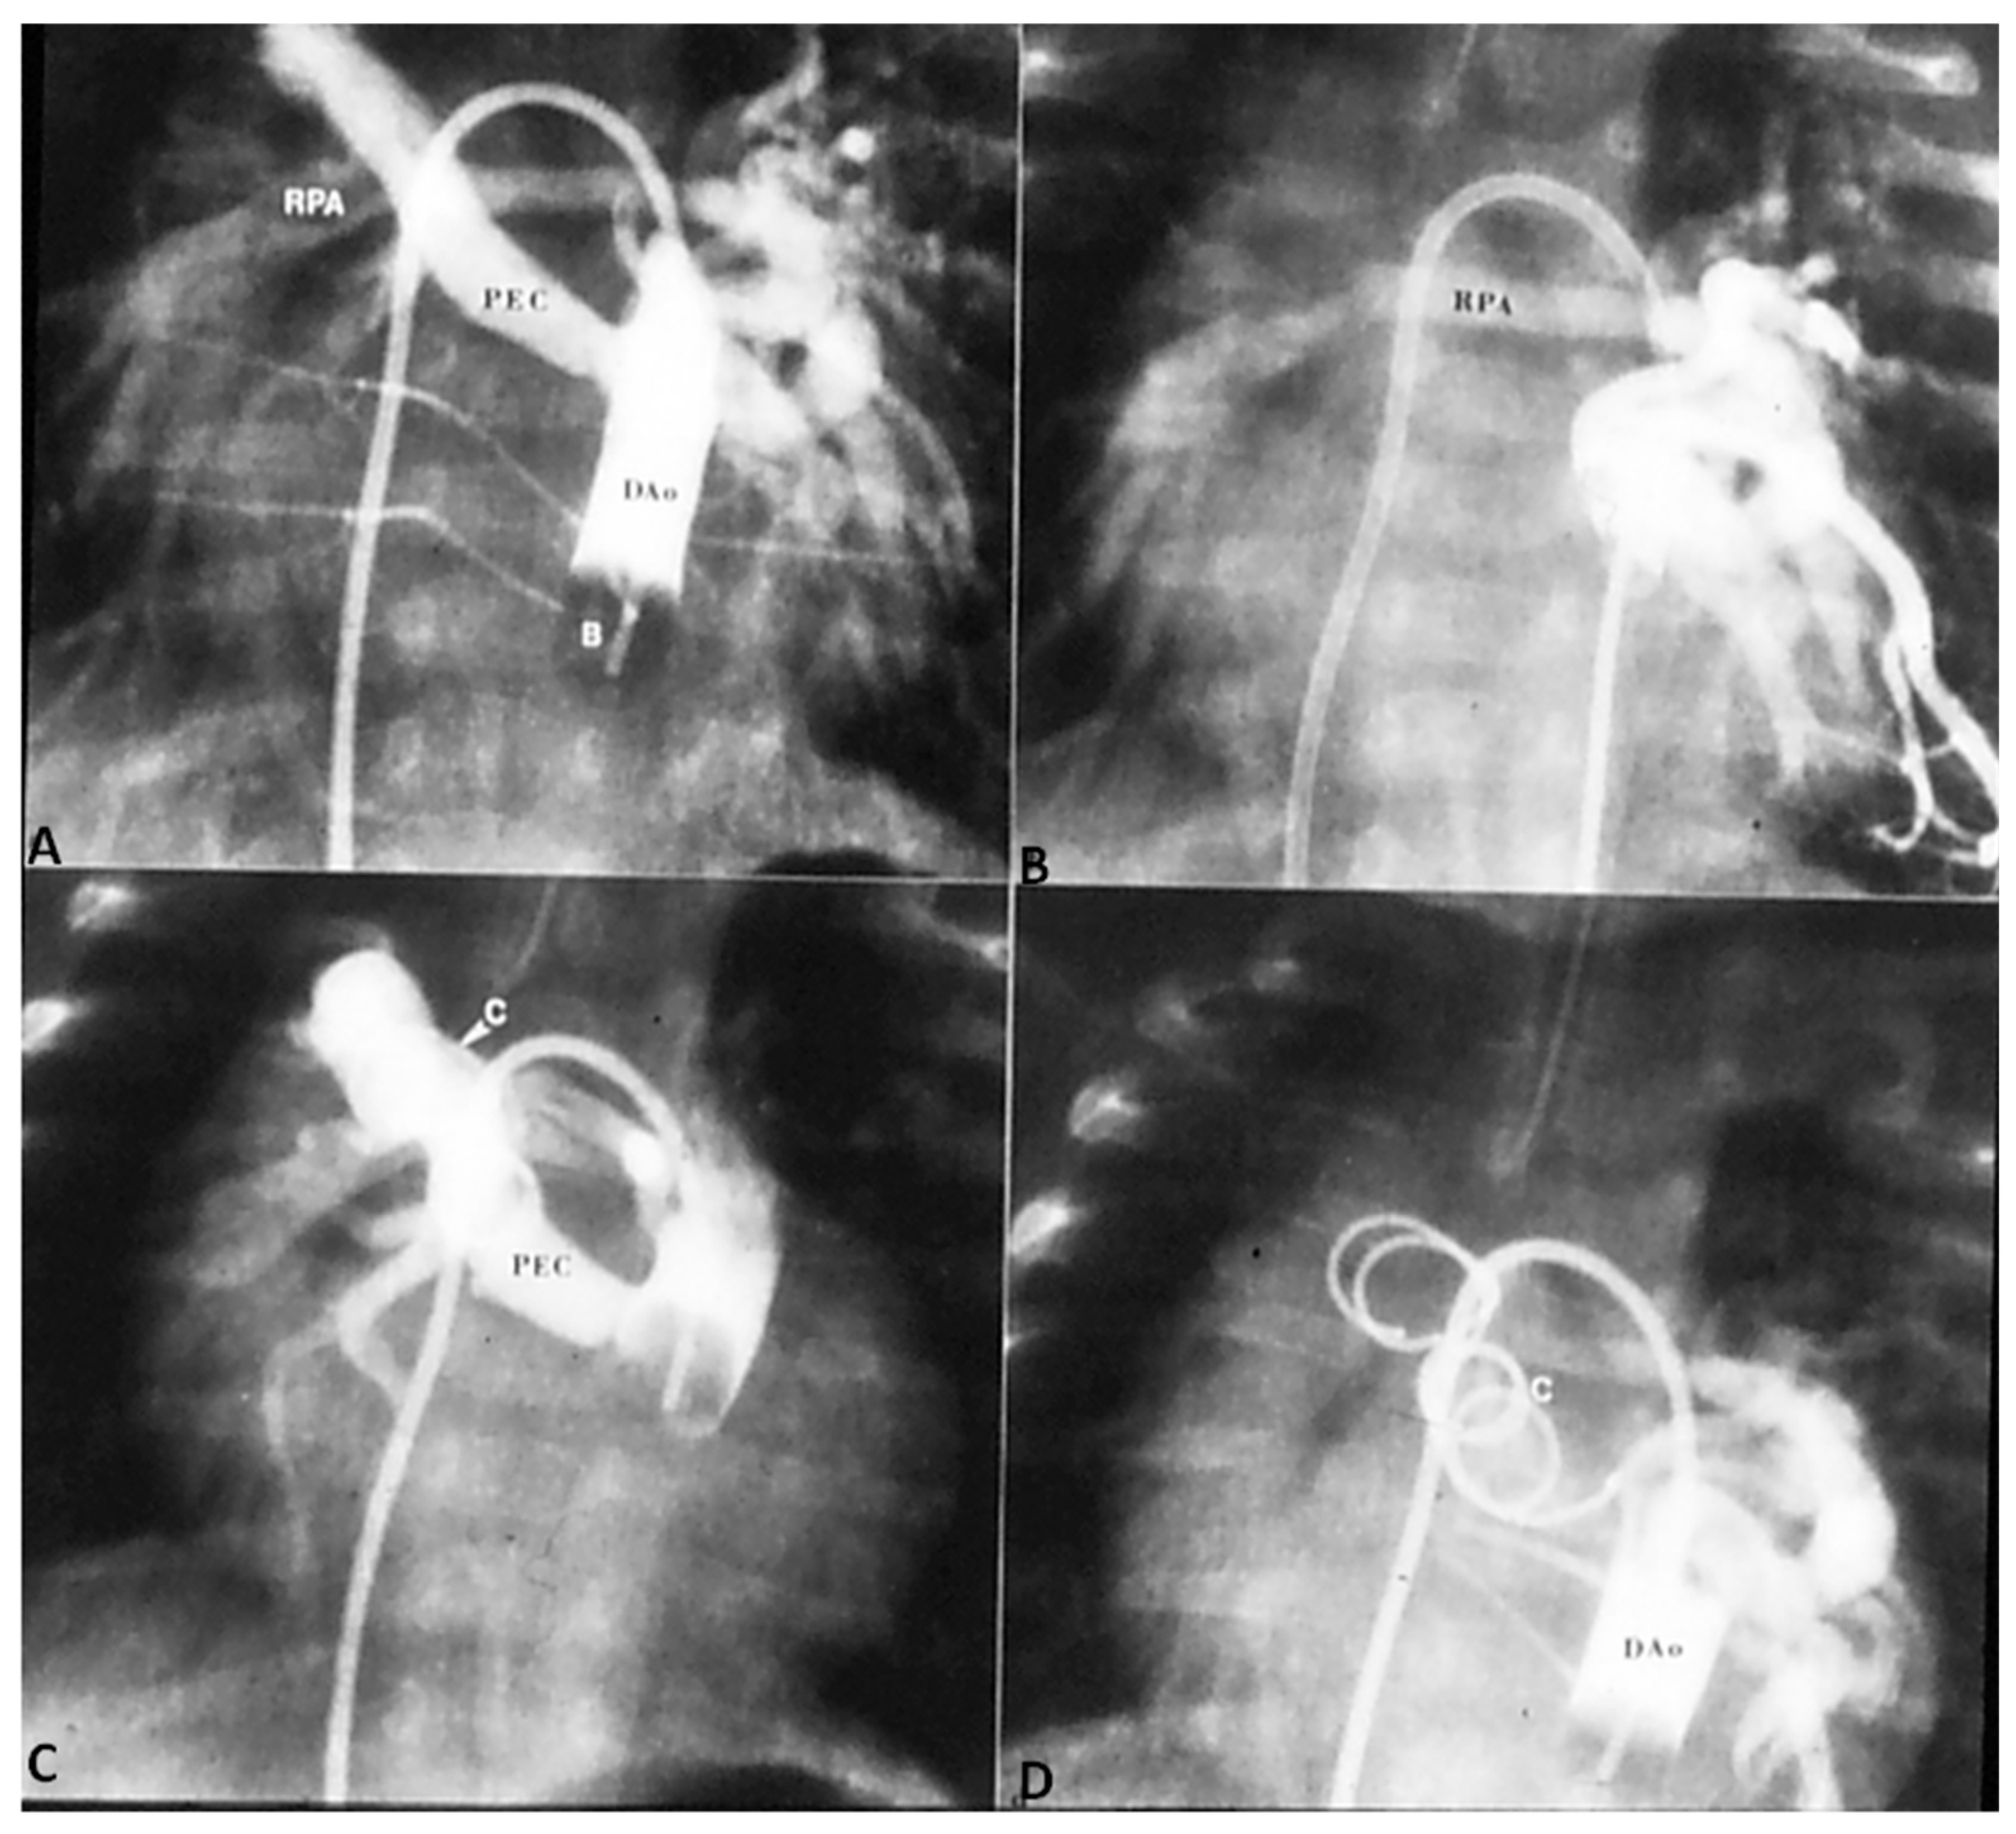

In patients with low O2 saturations and inadequate pulmonary blood flow, PGE1 infusion to open the ductus and/or an aortopulmonary shunt to augment the pulmonary blood flow may be required. In patients with adequate pulmonary blood flow with O2 saturations between 70% and 90% no immediate intervention is necessary. In patients with CHF, anti-congestive measures as detailed in Part 1 [1] should be instituted. Sometimes trans-catheter occlusion of a collateral vessel causing excessive pulmonary blood flow may needed (Figure 4) after ensuring that dual supply to the lung segments is present.

Once the baby is stabilized, cardiac catheterization and selective cine-angiography is performed to delineate the PA anatomy (atresia, degree of PA hypoplasia, confluence or lack of it), sources of pulmonary blood flow and degree of connections between central PAs and MAPCAs, and presence of dual supply to pulmonary arterial segments. If the native PAs are of adequate size (>50% of normal) and if the estimated RV systolic pressure following operation is less the 70% of LV systolic pressure, total correction is indicated. The latter assessments may be made by the use of McGoon ratio or Nakata index [33].

If the infant’s anatomy is not suitable for total surgical correction, staged reconstruction is contemplated. RV outflow tract is reconstructed with either a trans-annular patch or RV-to-PA conduit (usually a homograft) in an attempt to encourage growth of the native PAs. Such procedures also provide anterograde catheter access so that a more precise delineation of the pulmonary arterial tree can be undertaken and balloon angioplasty or stenting of PAs, as necessary, can be performed. Such interventions decrease RV pressures, augment flow to distal PAs and reduce ventilation/perfusion mismatch. Once adequate pulmonary blood flow is established the remaining aortopulmonary collaterals could be occluded by trans-catheter methodology, and the VSD is closed surgically.